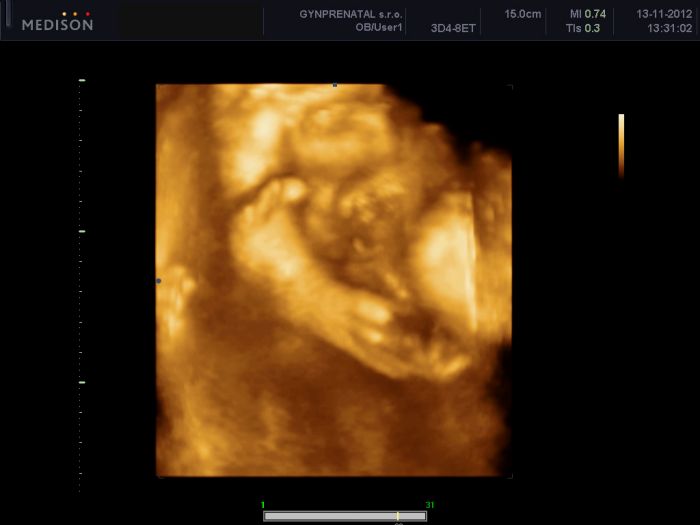

tak se konecne dnes taky hlasím. Byli jsme na tom 3D/4D ultrazvuku. Nachvilinku jsme videli obličejícek noa mame potvrzeného klučinu, pytlik tam byl jasný. Mohlabych se na tu fotečku dívat pořád.

[230016]Tet jsem si všimla, že je tam videt mezi tema nožičkama i toho potvrzeného klučinu

. Předtím jsem si ani nevšimla, jen jsem vam chtela ukazat ty roztomiloučké nožičky.

Jééé Danuš, krásné fotečky s pinďourkem

[230019] Jé, tak konečně vidím taky někde na UTZ fotce pindika a musim podotknout, ze toho my tam fakt nemame